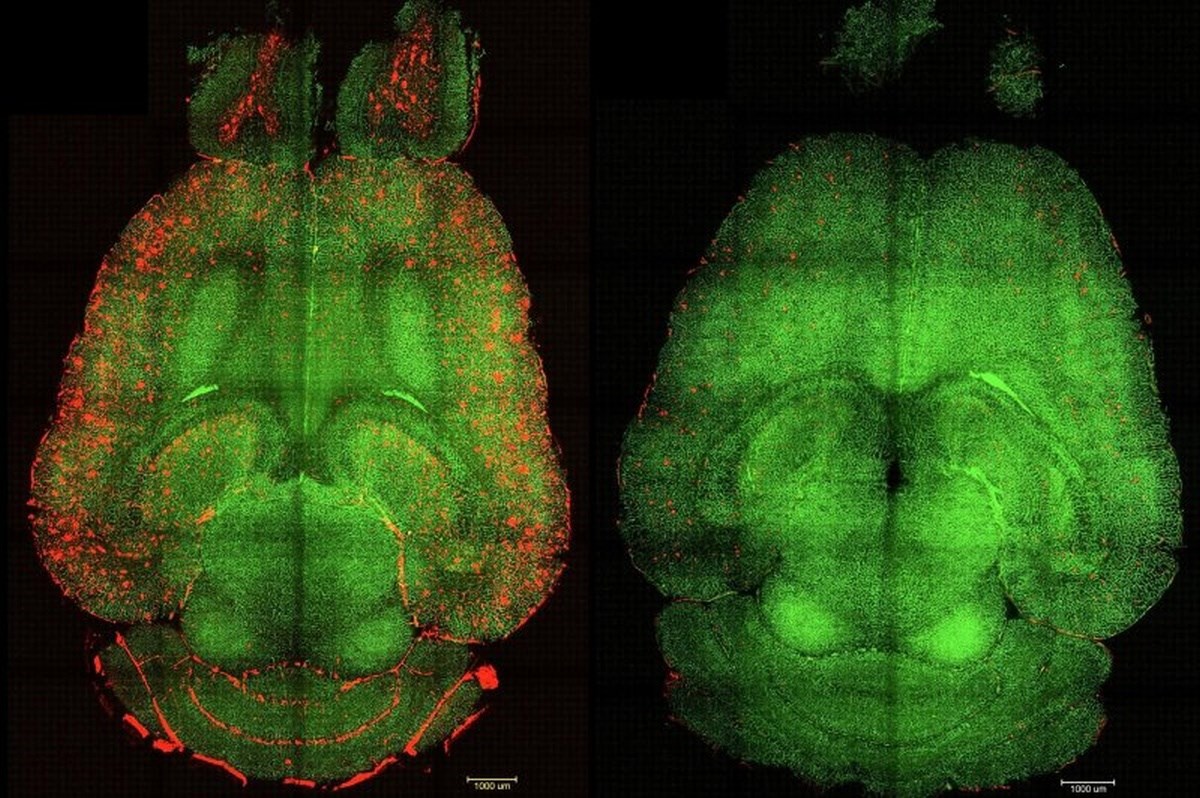

Krvno-moždana barijera štiti mozak od štetnih tvari, no kod Alzheimerove bolesti njezin integritet slabi. To omogućuje prodor toksina i nakupljanje štetnog proteina amiloid-beta, koji ometa prirodni sustav čišćenja mozga. Novi pristup omogućuje upravo tim proteinskim molekulama da prođu kroz obnovljenu barijeru i eliminiraju se putem krvotoka.

U nizu eksperimenata na genetski modificiranim miševima, koji proizvode velike količine amiloid-beta proteina i pokazuju pad kognitivnih funkcija, primjena supramolekularnih lijekova dovela je do gotovo trenutačnog smanjenja razine tog proteina. "Samo jedan sat nakon injekcije, primijetili smo smanjenje količine amiloid-beta proteina u mozgu za 50-60 posto", izjavio je koautor i istraživač iz Bolnice Zapadne Kine Sveučilišta Sichuan.

Posebno je uzbudljivo otkriće da su kognitivna poboljšanja kod miševa bila značajna. Miš, čija bi dob bila ekvivalent 90-godišnjeg čovjeka, "povratio je ponašanje zdravog miša" šest mjeseci nakon primanja tretmana. "Dugoročni učinak proizlazi iz obnove vaskulature mozga", objasnio je Battaglia.